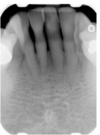

Well-defined apical radiolucency with loss of lamina dura – diagnosis?

A

• Periodontitis periapicalis chronica granulomatosa

• (chronic granulomatous apical periodontitis).

• Treatment: RCT or extraction

* Periodontitis periapicalis chronica granulomatosa * (Chronic granulomatous apical periodontitis) → Well-defined apical radiolucency, loss of lamina dura